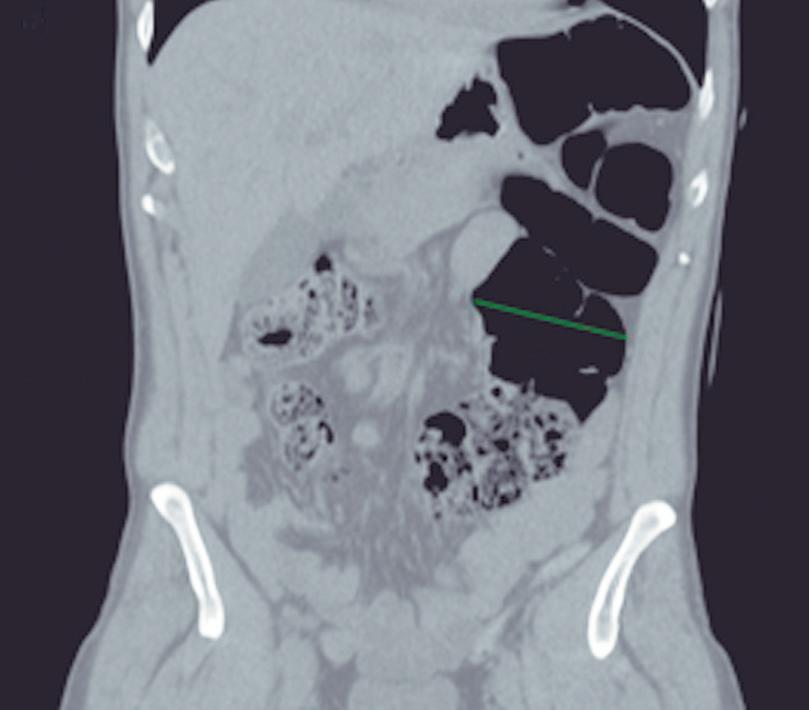

El páncreas anular en neonatos, cuando es sintomático, provoca síndrome de obstrucción gástrica, clínicamente manifestado con vómitos como consecuencia de la compresión y estenosis de la 2° porción duodenal. En los adultos también puede originar obstrucción gastrointestinal, y los pacientes presentan dolor abdominal, habitualmente postprandial y/o vómitos. En menor medida puede predisponer a PAR o bien a

Más allá del diagnóstico de esta anomalía debemos buscar signos imagenológicos indirectos de obstrucción gastrointestinal, como son la dilatación gástrica y de la 1° porción duodenal (Figura 10), con estrechez de la luz del duodeno en el sitio por donde transcurre a través del páncreas anular.18,19

A) Tomografía computada con contraste, plano coronal. El páncreas anular (flecha) provoca dilatación de la 1° porción del duodeno (cabezas de flecha). B) Tomografía computada con contraste, plano axial. Flechas: páncreas anular. Cabeza de flecha: duodeno. C) Tomografía computada con contraste, plano axial, corte más caudal que el previo. Flechas: páncreas anular.